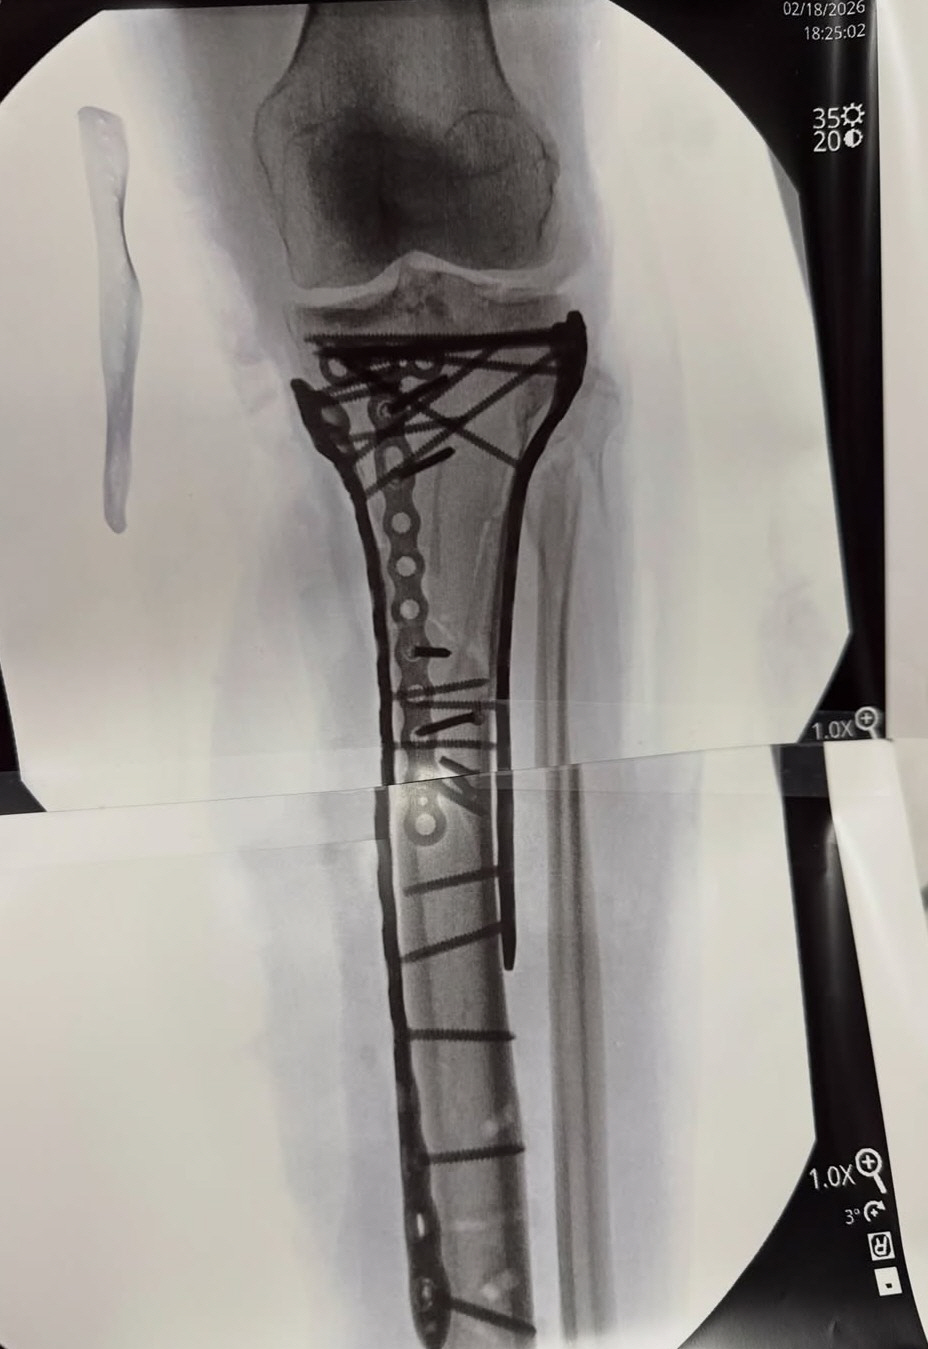

이탈리아에서 4차례나 수술을 받은 후 미국으로 돌아간 '스키 여제' 린지 본(42·미국)이 21일(이하 한국시각) 5차 수술을 끝낸 자신의 근황을 공개했다. 그는 자신의 SNS를 통해 '수술이 끝났다. 수술을 마치는 데 6시간 이상 걸렸다. 보다시피, 뼈를 고정하기 위해 많은 금속판과 나사가 필요했지만 헤켓 박사는 대단한 일을 해냈다'며 '많은 트라우마와 수술에 따른 통증으로 아직 퇴원하진 못했지만 거의 다 왔다. 부상과 어떤 의미의 수술인지는 곧 설명할 것'이라고 밝혔다.

일부에선 본의 상태에 대해 "다리를 절단할 수도 있다"고 우려했다. 그는 이탈리아에서 4차례나 수술대에 올랐다. 미국으로 귀국해 장시간에 걸쳐 뼈 고정 수술을 받은 것으로 보인다. 본은 수술 후 병상에 누워 이동하는 영상과 함께 금속판과 나사가 박힌 엑스레이 사진을 공개했다.